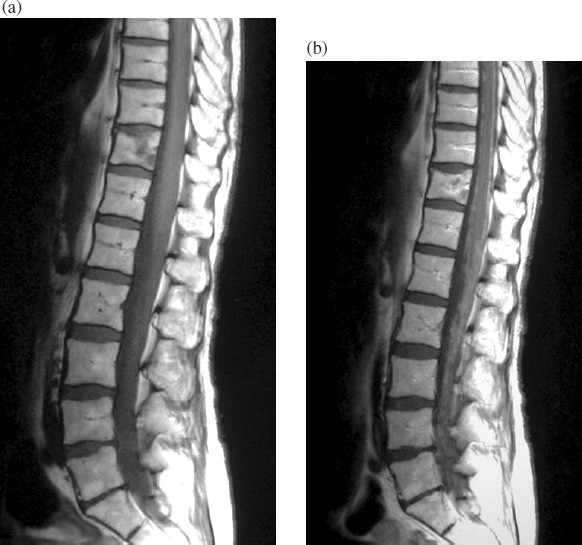

Spinal And Meningeal Metastatic Disease | Cancer Imaging | Full Text

Spinal and meningeal metastatic disease | Cancer Imaging | Full Text cancerimagingjournal.biomedcentral.com

meningeal metastatic